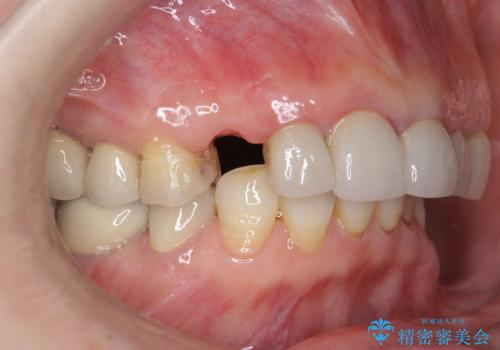

クラウン下に再発した深い虫歯 インプラントによる機能回復

- 定期検診で通院されていたところ、20年前に他院で治療した前歯のセラミック歯の下に深い虫歯が再発していることがわかりました。

ブリッジや歯の挺出を行い保存する提案も行いましたが、短期間の定期的な通院が難しくインプラントによる少ない回数での治療を希望されました。